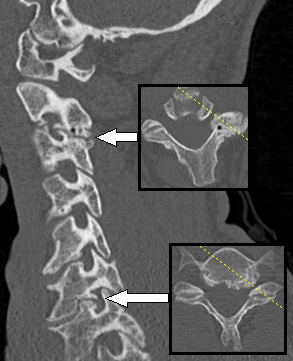

신경근병증은 일반적으로 신경근이 출구 추간공이나 가쪽 함요에서 기계적으로 압박되어 발생한다. 이는 추간판 탈출증(가장 흔하게는 C7, 그 다음은 C6 레벨), 퇴행성 디스크 질환, 골관절염, 후관절 변성/비대, 인대 비대, 척추전방전위증 또는 이러한 요인들의 조합으로 인해 발생할 수 있다.[3][4] 환자에게서 관찰되는 신경근병증의 경우 대개가 C6-C8 지점에 가까운 경추에 위치한다.[29]

보존적 치료 4~6주 후에도 증상이 호전되지 않거나 환자가 50세 이상인 경우 추가 검사가 권장된다.[3] 미국 방사선 학회는 만성 목 통증이 있는 모든 환자에게 투사 방사선 촬영술이 가장 적절한 초기 검사라고 권장한다.[13] 유용할 수 있는 두 가지 추가 진단 검사는 자기 공명 영상과 전기 진단 검사이다. 신경근병증이 의심되는 척추 부위의 자기 공명 영상 (MRI)은 환자의 증상을 유발하는 퇴행성 변화, 관절염 질환 또는 기타 설명 가능한 병변의 증거를 나타낼 수 있다. NCS (신경 전도 검사)와 EMG (근전도 검사)로 구성된 전기 진단 검사는 의심되는 부위에서 신경근 손상을 보여줄 수 있는 강력한 진단 도구이다. 신경 전도 검사에서 복합 근육 활동 전위 감소 및 정상 감각 신경 활동 전위 패턴은 병변이 후근 신경절에 근접해 있을 때 나타날 수 있다. 바늘 EMG는 더 민감한 검사 부분이며, 관련된 신경근의 분포에서 활성 탈신경을 나타낼 수 있으며, 만성 신경근병증에서는 신경성으로 보이는 자발적 운동 단위가 나타날 수 있다. 급성 및 만성 신경근병증 진단에서 전기 진단 검사의 핵심적인 역할을 고려하여, 미국 신경근 및 전기 진단 의학회는 경추 및 요천추 신경근병증 진단에 대한 증거 기반 진료 지침을 발표했다.[14][15] 미국 신경근 및 전기 진단 의학회는 또한 현명한 선택 캠페인에 참여했으며, 이들의 권고 중 일부는 목과 허리 통증에 불필요한 검사와 관련이 있다.[16]